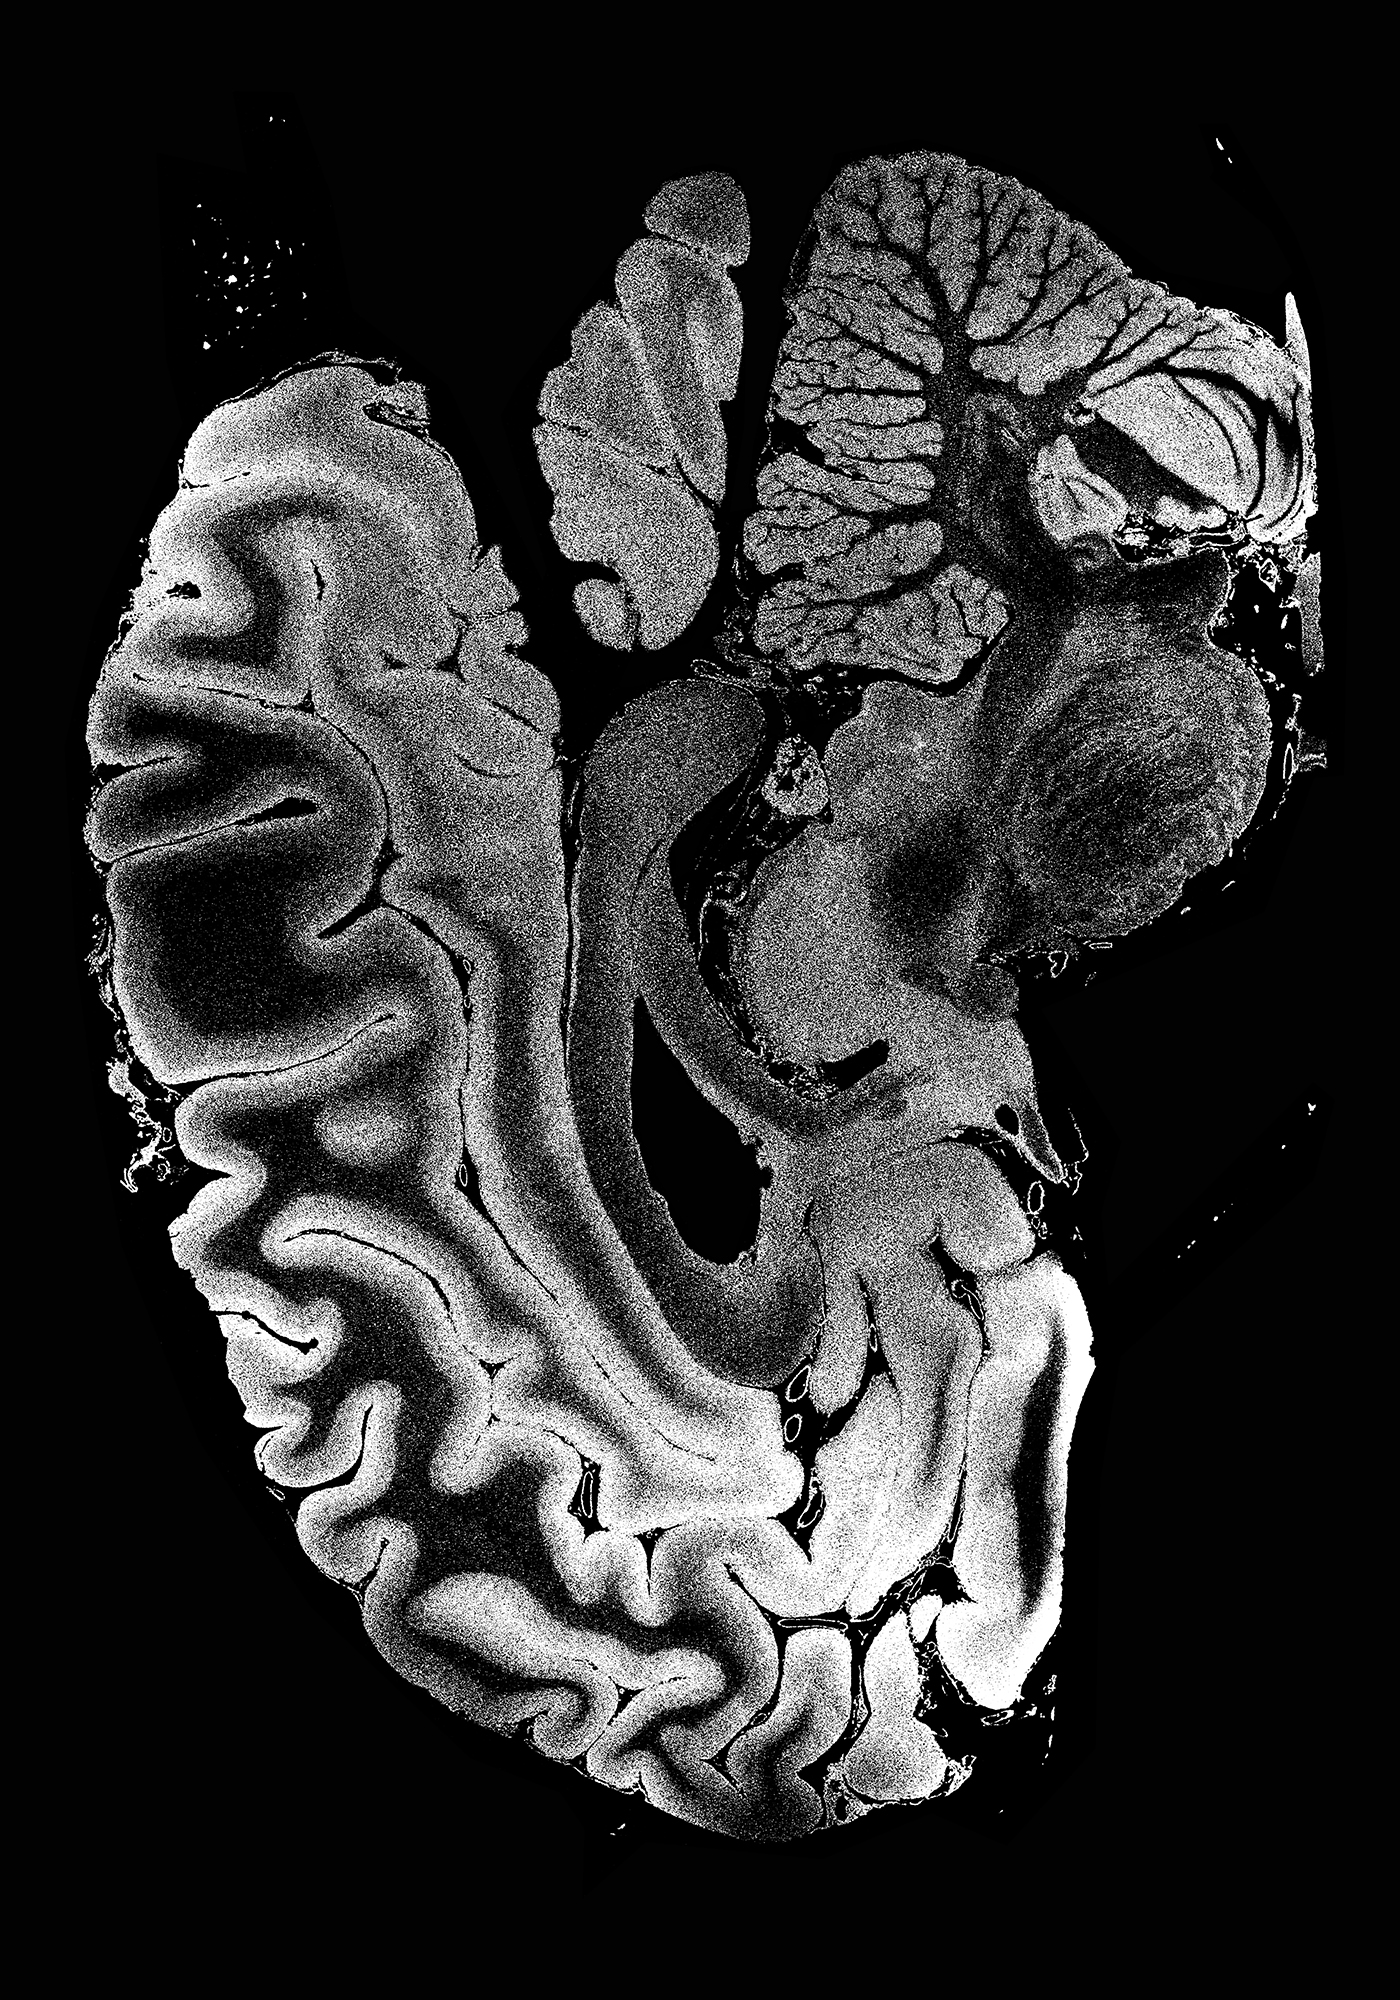

No man is an island2022Ink on paper50 x 70 cmconceptual, print, bw